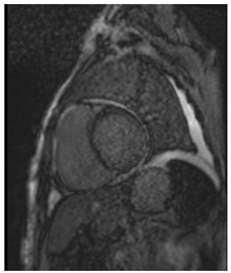

| CMR Parameter | Key CMR Findings | Illustrative Example |

|---|---|---|

| Cardiac Structure and Function |

| ![]() |

| T1 time | Native T1 time may be focally increased in regions of fibrosis or edema | ![]() |

| T2 Time | T2 time may be focally increased in regions of edema | ![]() |

| LGE |